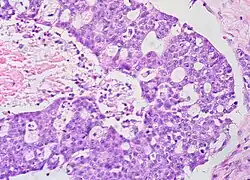

Immature (solid) teratoma

.jpg)

Immature, or solid, teratomas are the most common type of ovarian germ cell tumor, making up 40–50% of cases. Teratomas are characterized by the presence of disorganized tissues arising from all three embryonic germ layers: ectoderm, mesoderm, and endoderm; immature teratomas also have undifferentiated stem cells that make them more malignant than mature teratomas (dermoid cysts). The different tissues are visible on gross pathology and often include bone, cartilage, hair, mucus, or sebum, but these tissues are not visible from the outside, which appears to be a solid mass with lobes and cysts. Histologically, they have large amounts of neuroectoderm organized into sheets and tubules along with glia; the amount of neural tissue determines the histologic grade. Immature teratomas usually only affect one ovary (10% co-occur with dermoid cysts) and usually metastasize throughout the peritoneum. They can also cause mature teratoma implants to grow throughout the abdomen in a disease called growing teratoma syndrome; these are usually benign but will continue to grow during chemotherapy, and often necessitate further surgery. Unlike mature teratomas, immature teratomas form many adhesions, making them less likely to cause ovarian torsion. There is no specific marker for immature teratomas, but carcinoembryonic antigen (CEA), CA-125, CA19-9, or AFP can sometimes indicate an immature teratoma.[32]

Stage I teratomas make up the majority (75%) of cases and have the best prognosis, with 98% of patients surviving five years; if a Stage I tumor is also grade 1, it can be treated with unilateral surgery only. Stage II though IV tumors make up the remaining quarter of cases and have a worse prognosis, with 73–88% of patients surviving five years.[32]